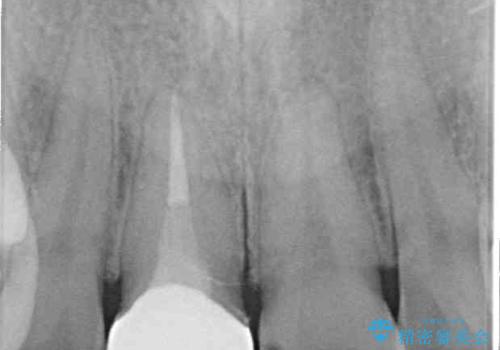

根管治療された状態に大きな問題はなかったため、土台を植立し、オールセラミッククラウンにて補綴治療を行うこととしました。

オーダーメイドタイプのクラウンを選択されたため、周辺の歯と調和が取れる色合いとなるまで修正を繰り返しました。